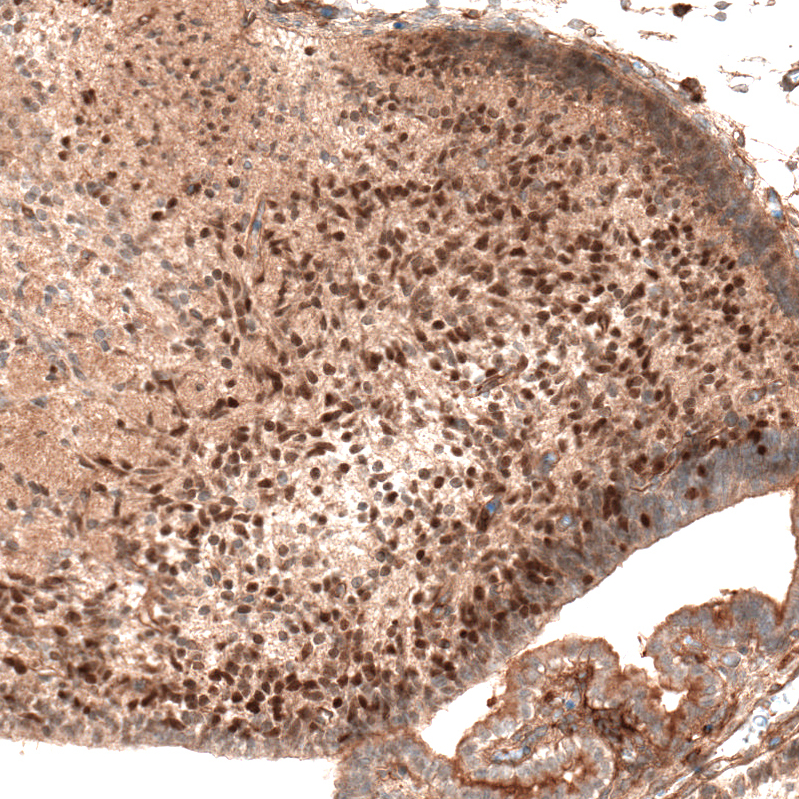

Immunohistochemical staining of mouse embryo E14 shows moderate nuclear positivity in neuronal cells in the developing cerebellum.